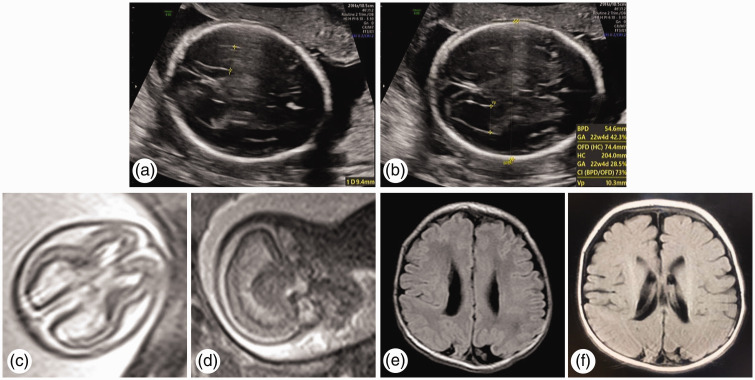

单绒毛膜单羊膜双胞胎妊娠是非常罕见的,经常导致并发症。然而,在单绒毛膜单羊膜双胎妊娠中,没有单胎宫内死亡后存活胎儿肺损伤的报道。据我们所知,我们首次报道了单绒毛膜单羊膜双胎妊娠中单个宫内胎儿死亡后存活胎儿的肺和脑损伤。一名男婴出生时呼吸困难。他健康的39岁母亲是单绒毛膜单羊膜双胎妊娠。一个胎儿在妊娠17+2周心脏骤停后,存活的胎儿从19周开始出现轻微的双侧心室扩张。通过剖宫产与死亡胎儿一起分娩,存活的胎儿表现出肺和脑损伤,并在10天大时出院。在排除其他新生儿疾病后,他的长期炎性肺损伤被认为与单一宫内胎儿死亡有关。本病例提醒妇产科医生,单胎宫内死亡可引起单绒毛膜单羊膜双胎存活胎儿肺吸入和脑缺血-缺氧损伤。产前评估和产后随访对这类高危妊娠至关重要。

Pregnancy with monochorionic monoamniotic twins is highly rare and frequently results in complications. Nevertheless, in monochorionic monoamniotic twin pregnancies, there are no reports of lung injury in the surviving fetus after single intrauterine fetal death. To the best of our knowledge, we present the first report of lung and brain injuries in a surviving fetus after single intrauterine fetal death in a monochorionic monoamniotic twin pregnancy. A male child was born with dyspnea. His healthy 39-year-old mother had a monochorionic monoamniotic twin pregnancy. After the cardiac arrest of one fetus at 17+2 weeks of gestation, the surviving fetus showed slight bilateral ventricular dilatation from 19 weeks. Delivered full-term alongside the deceased fetus via cesarean section, the surviving fetus exhibited lung and brain injuries and was discharged at 10 days old. His prolonged inflammatory lung injury was considered related to single intrauterine fetal death, after ruling out other neonatal conditions. This case reminds obstetricians and pediatricians that single intrauterine fetal death could cause pulmonary inhalation and cerebral ischemic-hypoxic injury in monochorionic monoamniotic twin surviving fetuses. Antenatal evaluation and postnatal follow-up are essential in this type of high-risk pregnancy.